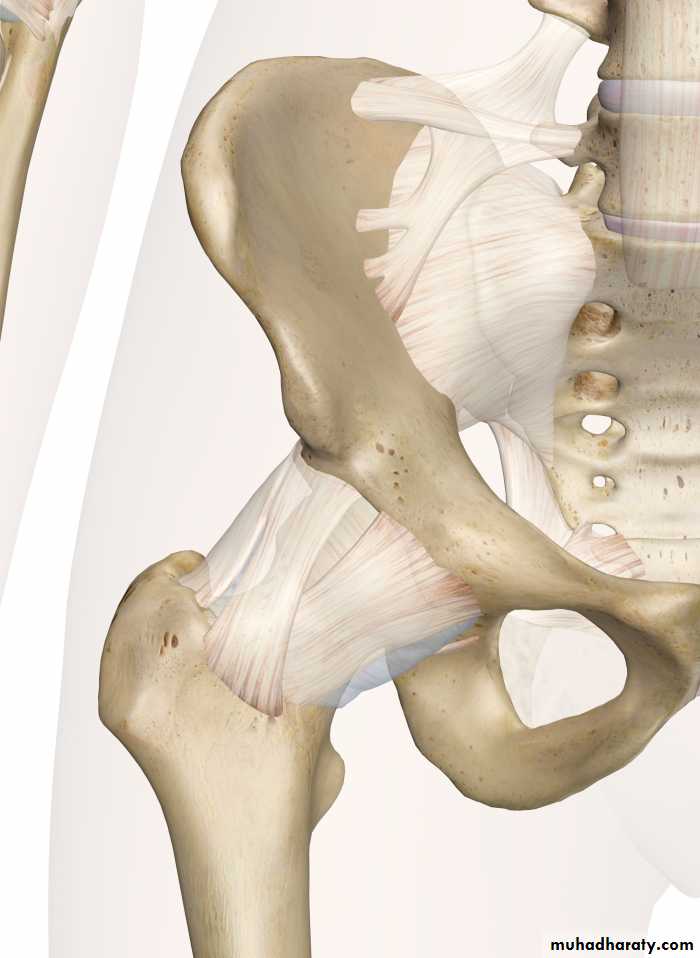

Practical Anatomy of The Lower Limbs for 1st Year Students

Prof.Dr.Abduljabar Alhubaity

Dep.of Anatomy/College of Medicine

University of Mosul